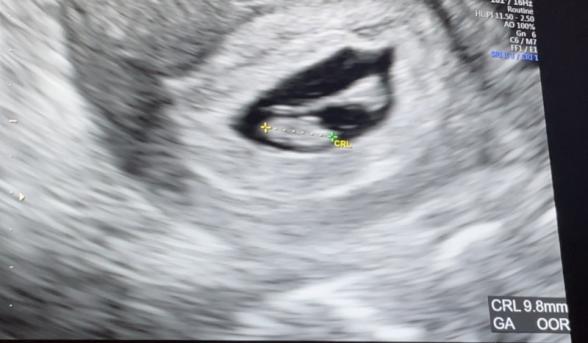

胎芽の隣にある影について

赤ちゃんの写真拝見しましたが、このお写真だけで、ママさんが疑問のものが何であるかを判断するのは難しいです。

申し訳ありません。

また医師にも聞いてみてくださいね。